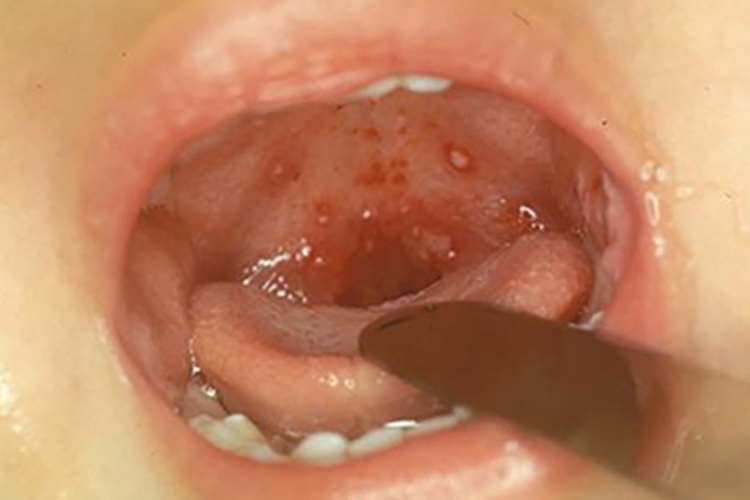

咽峡炎多起病急骤,疾病发生后,部分患者咽峡可出现红肿的表现,同时伴有发热、咽痛、咽干、异物感等症状,有些患者可在咽部出现白色疱疹,需尽早就医治疗。

咽峡炎病因复杂,可由病原体感染引起,如病毒感染、细菌感染,常见于柯萨奇病毒A型,或梭形杆菌、樊尚螺旋菌等。